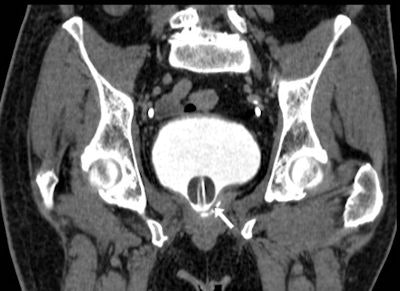

Image from MDCT cystography acquisition in a 73-year-old postoperative patient after robot-assisted laparoscopic radical prostatectomy shows sufficient bladder distension and opacification of a minimal extraperitoneal leak at the vesico-urethral anastomosis (arrow). Applied with care in the early postoperative setting, this technique can allow confident detection or exclusion of urine extravasation indicating lower urinary tract injury both spontaneous (such as in colovesical fistulas from diverticulitis) and iatrogenic.In urologic patients, a postoperative MDCT study should include a preliminary unenhanced acquisition to detect hyperattenuating blood and abnormal air collections, arterial and venous-phase images after intravenous contrast medium (CM) injection to assess the solid organs and identify extravascular CM indicating active bleeding, and excretory phase imaging. Images are obtained at least 5 minutes to 20 minutes (up to 1-2 hours) after CM, in order to demonstrate the opacified urinary cavities and detect iodinated urine leaks and urinomas, they wrote.

"Due to its intrinsically high contrast resolution, MRI provides excellent visualization of the normal postprostatectomy anatomy and of possible neoplastic recurrence. In the emergency setting, the use of MRI is limited by lengthy examination time, scanner availability, constraints, and artifacts in acutely ill patients," wrote the authors. "Compared to MRI, with appropriate acquisition techniques MDCT provides quicker reliable identification of blood collections, extravasated urine, and active bleeding. Furthermore, in patients with suspicion of VUA leak an additional focused investigation with conventional radiographic cystography or MDCT cystography is recommended."

In their department, diluted iodinated CM used during MDCT cystography is prepared by removing 40 mL to 50 mL of normal saline from a 500-mL bag and injecting a similar amount of nonionic contrast agent (e.g., 350 mgI/mL iomeprol or 370 mgI/mL iopromide) into the same saline solution bag. The bag is then connected to standard tubing for intravenous infusions, filling the tube with diluted contrast to avoid instilling air in the bladder. With the patient supine on the CT scanner table, slow retrograde infusion is obtained by gravity.

The injected CM volume should not exceed 150 mL, according to the group. The volumetric MDCT acquisition at sufficient bladder distension is visualized with multiplanar image reformations at CT angiography window settings (width 600-900 level 150-300 Hounsfield Units) and by maximum intensity projection or 3D techniques. The only potential pitfall of this technique is the possible occlusion of a limited anastomotic dehiscence by the Foley catheter balloon, they added.